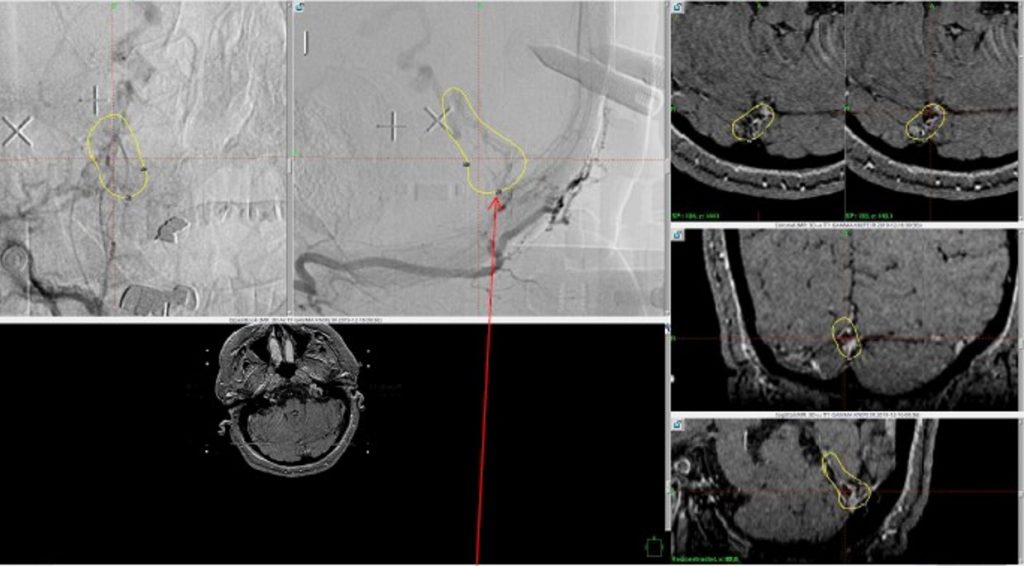

Figure 6. MRI and Catheter Angiograms precisely localize the residual A-V shunts vessels to perform Gamma-Knife Radiosurgery to deliver therapeutic doses to the targets.